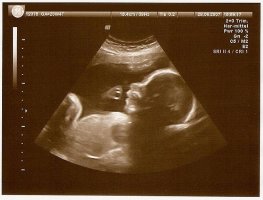

Ich war am Donnerstag endlich beim Feindiagnost-Ultraschall. Insgesamt 4 Stunden, davon 3 Stunden Wartezeit; hätte ich das vorher gewusst, hätte ich mir was zu Essen mitgenommen.

Ich bekam 2 US von 2 verschiedenen Ärzten; soweit ist bei dem Krümel alles in bester Ordnung.

Aber... der erste Arzt meinte, es wird ein Mädchen, und die zweite Ärztin meinte dann, es wird ein Junge :sn7

Insofern habe wieder mal eine gute 50/50 Chance...

Aber ich glaube, dass die Prognose der Ärztin, dass es ein Junge wird, wahrscheinlicher ist. Naja. Dann mal noch einen Bildanhang.

• 24te Woche.jpg